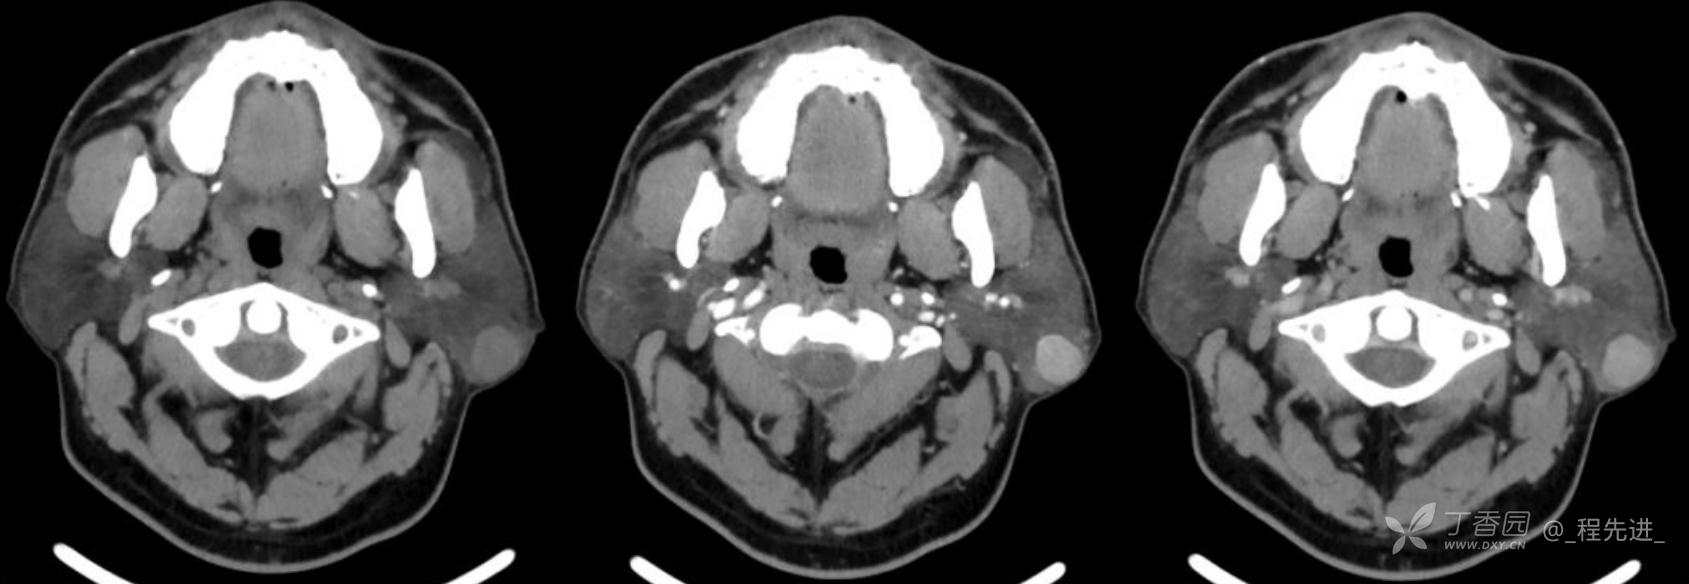

患者性别:男

患者年龄:38岁

简要病史:病程1年,1年前发现左耳后肿物,无发热疼痛不适,未见明显增大,入院

辅助检查:实验室各项指标未见明显异常